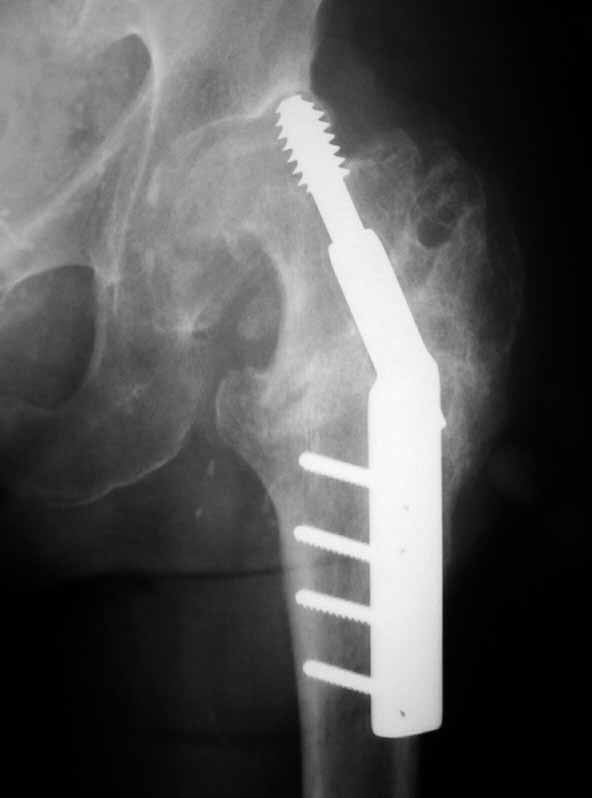

يبدأ علاج خشونة الورك بالعلاج التحفظي، وفي حال عدم تحسن المريض مع وجود مراحل متقدمة في الاحتكاك فيكون الحل في العلاج الجراحي، وهو عبارة عن استبدال كامل لمفصل الورك بواسطة المفاصل الصناعية. حيث تعتبر من اكثر العمليات نجاحاً وبنتائج مذهلة